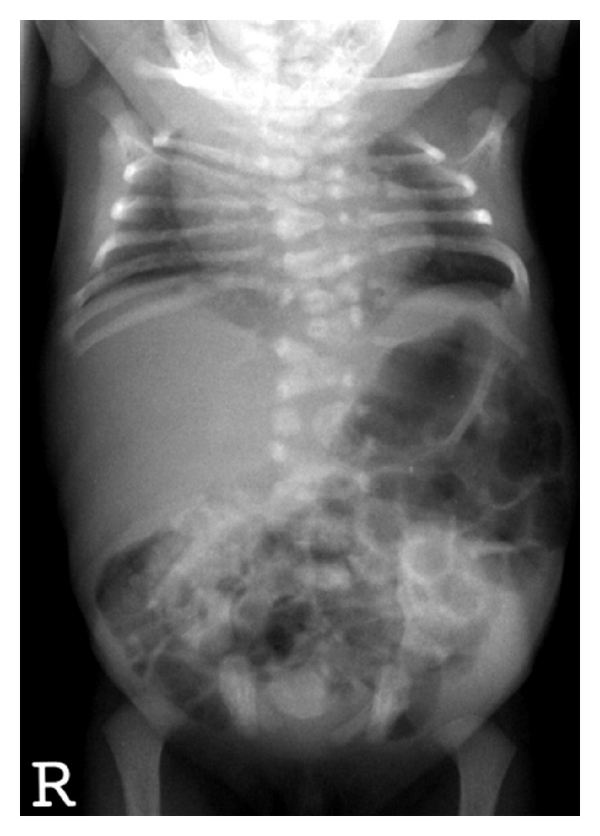

Mutations in Notch signaling genes have been identified in two monogenic forms of CVM. Spondylocostal dysostosis (SCD) is an autosomal recessive disorder, with occasional autosomal dominant inheritance. Radiographically, SCD is characterized by contiguous vertebral segmentation defects in addition to rib abnormalities Figure 5. Affected individuals have disproportionate short stature, characterized by a shortened trunk and protuberant abdomen. Associated features include scoliosis and mild respiratory compromise. Mutations in DLL3, a Notch pathway signaling gene, were identified in Arab-Israeli and Pakistani kindreds using synteny conversion analysis [59]. Mutations in Notch signaling pathway genes, including MESP2 [60], LFNG [61], and HES7, have subsequently been identified [62]. The term “pebble beach” sign refers to morphologically abnormal vertebral bodies characterized by a smooth, round contour, usually associated with the presence of a DLL3 mutation [63]. Hypoplasia of the left vertebral artery has been reported in one affected individual with a compound heterozygous mutation in HES7 (158D/V186Y).